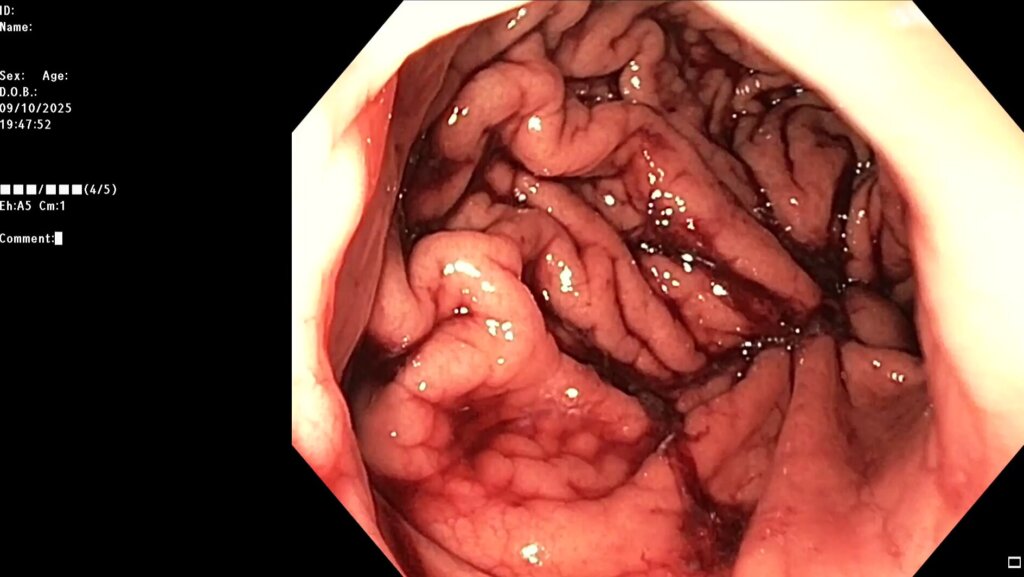

Под видеоконтролем выполнена эндоскопическая рукавная гастропластика: сшивание стенок желудка при помощи аппарата Overstitch Boston Scientific по длине тела с целью уменьшения объёмов съедаемой пищи.

Комбинированный метод представляет собой эндолюминальное ушивание желудка (формирование «рукава») с добавлением локальной аргоноплазменной коагуляции (АПК, APC — поверхностная неконтактная термальная абляция слизистой) в зоне свода желудка с целью индуцирования контролируемого фиброза и снижения секреции грелина. ESG выполняется перорально под визуальным контролем с использованием системы Overstitch;